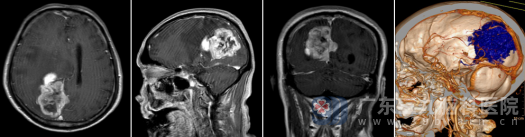

入院后,神经外十科团队迅速为冯先生完善了术前评估。检查结果触目惊心:术前MR显示,肿瘤大小约为66×40×54mm,已占据右侧顶枕部镰旁空间;术前CTA更是揭示了一个巨大的挑战——肿瘤内部及周围有大量异常血管穿行、缠绕,血供极其丰富,宛如一团盘根错节的“肉血球”,并紧挨着重要的脑功能区。

“肿瘤附着面紧贴大脑镰,周围都是重要的回流静脉,稍有不慎就可能导致术中大出血或术后严重神经功能障碍。”手术医生介绍,这场手术无异于在“生命中枢”旁拆弹,对主刀医生的显微操作技术、解剖功底和心理素质都是极大考验。

经过周密的术前规划和多学科讨论,一场历时7个多小时的攻坚战悄然打响。手术在显微镜下精细操作,在欧阳辉教授和林德留主任的领导下抽丝剥茧,精雕细刻,一点一点地将肿瘤从被浸润的脑膜和血管上剥离,既要彻底切除病变,又要毫发无损地保护周围正常的脑组织及至关重要的血管。经过长达7个小时的鏖战,肿瘤终于被完整切除。